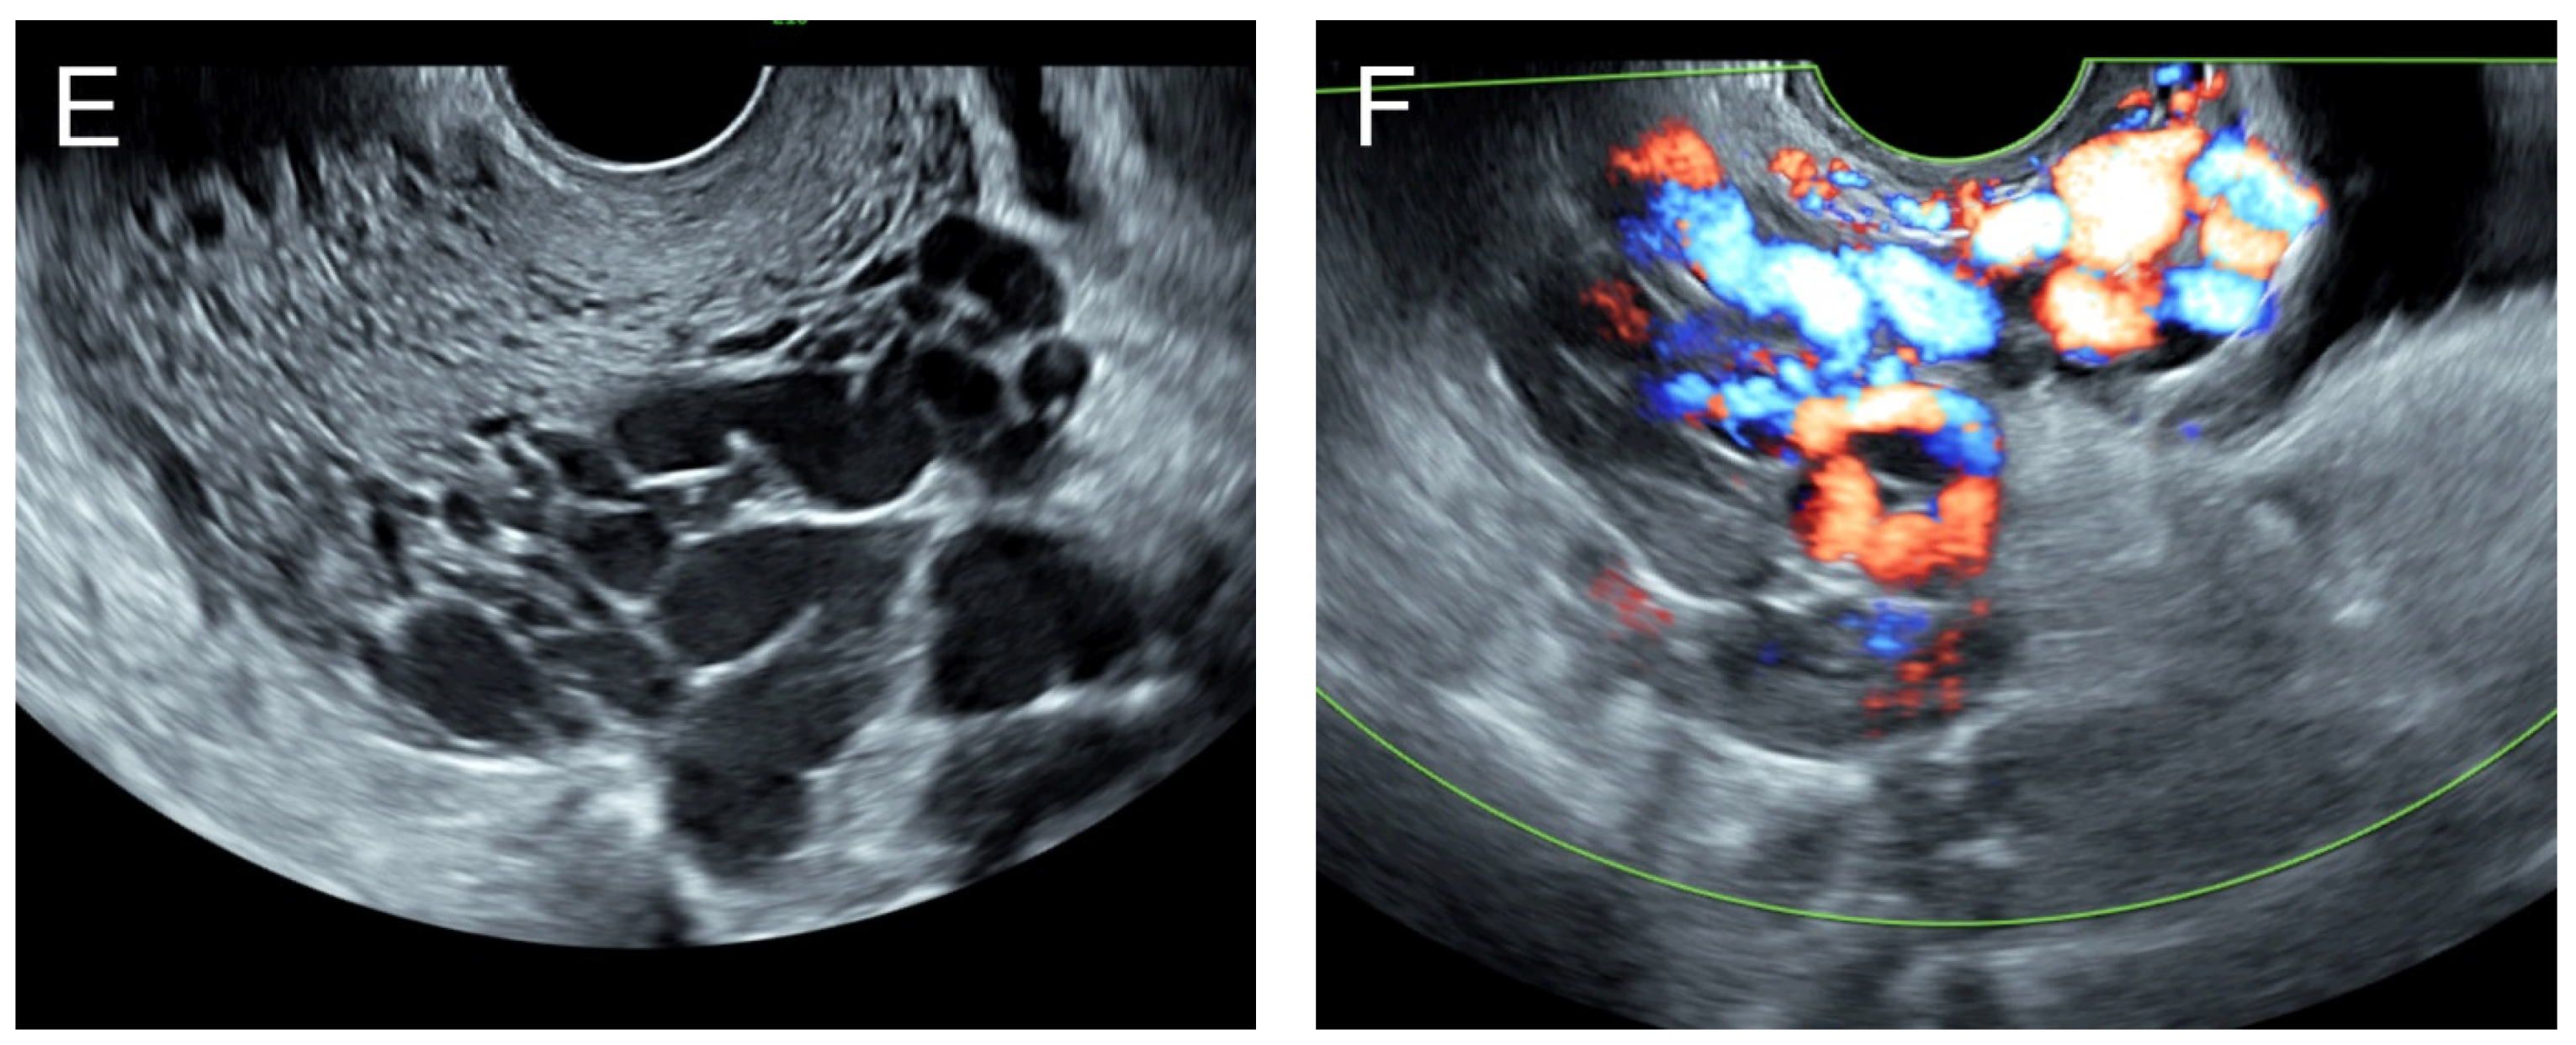

3. Case 2 (Figure 2)

Figure 2. (A) Transabdominal grayscale ultrasound: transverse scans of suprapubic area showed suboptimal-quality image of the uterus, which displayed ill-defined soft tissue mass, non-visualized endometrial lining, hypoechoic areas of the uterus. No normal architecture of the uterus could be demonstrated. (B) Color flow mapping (the same area of figure (A)) showed markedly vascularized uterus, involving throughout the uterus intense vascularity with a chaotic, multidirectional flow. (C) Transvaginal color Doppler ultrasound showed markedly vascularized uterus, involving throughout the uterus intense vascularity with a chaotic, multidirectional flow. (D) Abdominal CTA revealed innumerable tortuous dilated vessels in the pelvic cavity, along the entire uterine wall. The lesions were fed by multiple arterial feeders, which were displayed as tortuous dilated arteries of the bilateral uterine arteries, right ovarian artery, and right inferior epigastric artery. Multiple draining veins demonstrated early venous opacification, namely the bilateral internal iliac veins and right ovarian vein. The CTA findings confirmed uterine AVM.

Management: Initial therapy included fluid resuscitation, blood transfusion, and tranexamic acid administration. Transcatheter uterine embolization of the bilateral uterine arteries, right ovarian artery, and right inferior epigastric artery was successfully performed, without immediate post-operative complications. The follow-up abdominal CTA at 8 weeks after the procedure showed no residual AVM, and the patient was healthy with no further abnormal bleeding at 2.5-year follow-up.